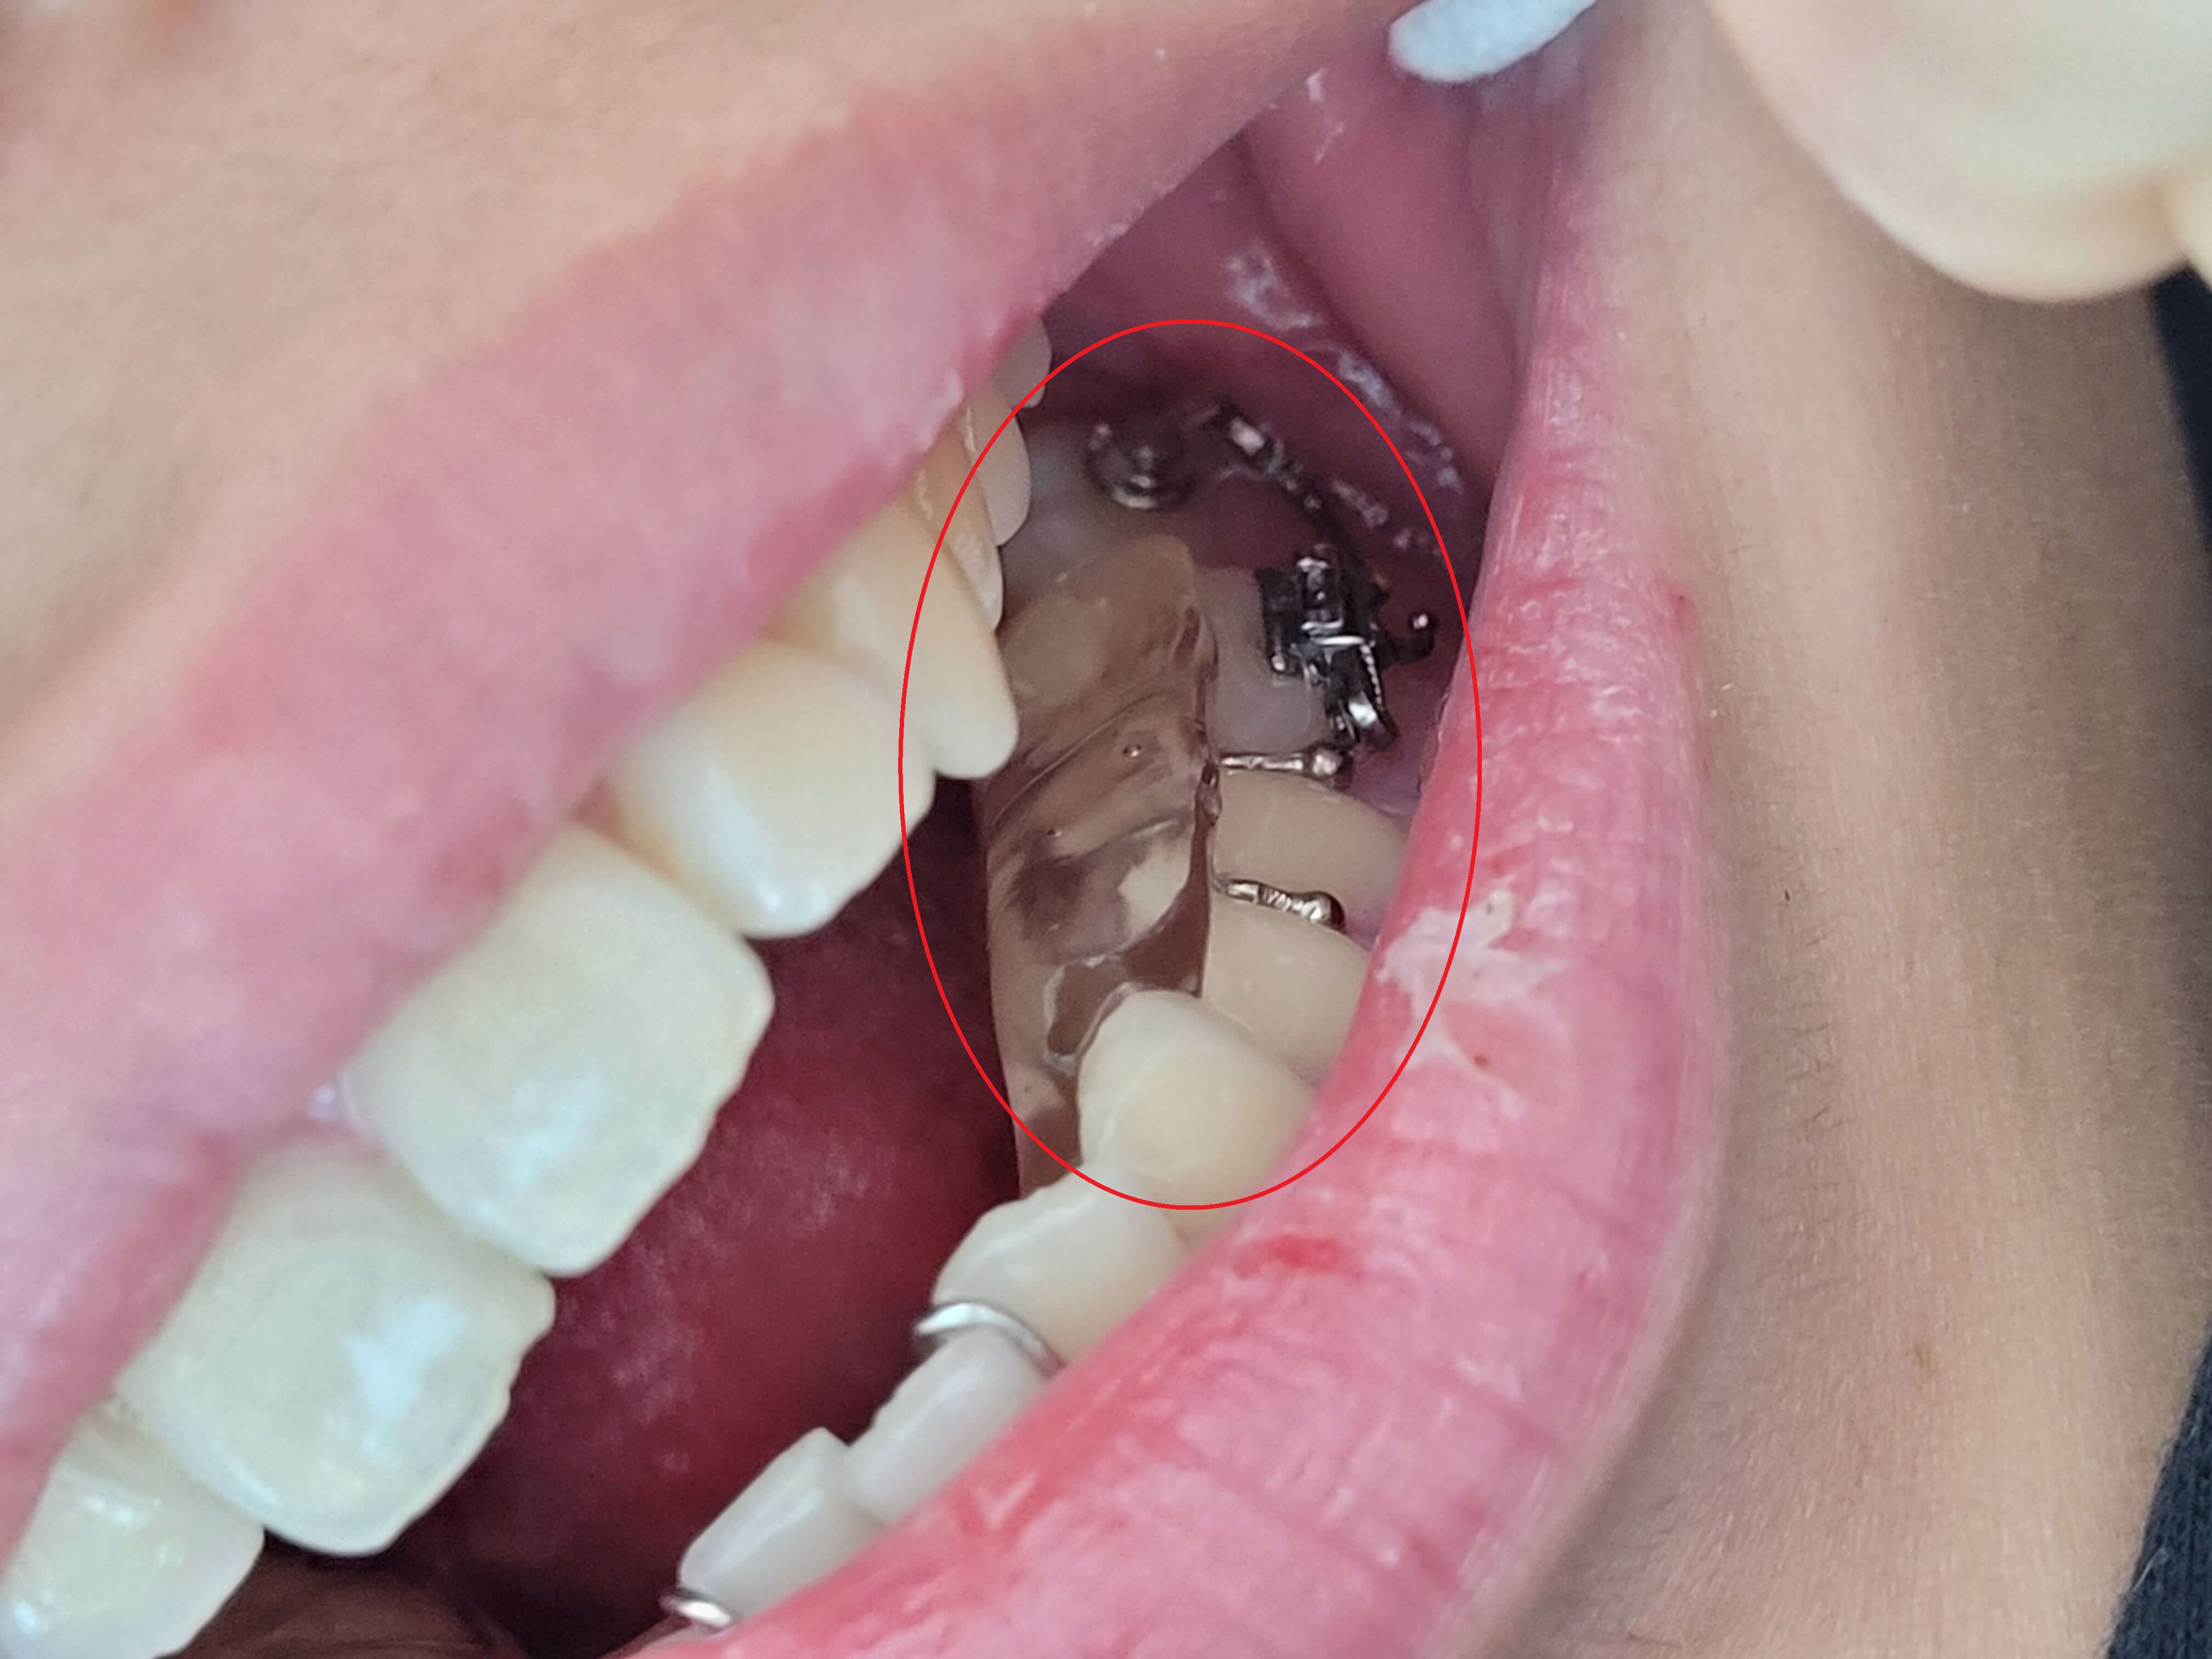

◎ 아들치아교정 전 상태확인 (가위교합사진)

- 「윗 어금니 가위교합 1개」

- 「아래 어금니 가위교합 1개」

저는 치아가 자유로이 움직인다는 것을 처음 알았습니다. 그리고 복원력이 있다는 것도 알게 되었는데요. 사진에서 보듯이 어금니가 옆으로 누워있습니다.

위, 아래 어금니가 모두 그렇는데 아래 어금니는 브라켓 설치로 힘을 주어 잡아당기고 있고 윗 어금니는 스크류를 박고 고무줄(체인)로 잡아당기고 있습니다.